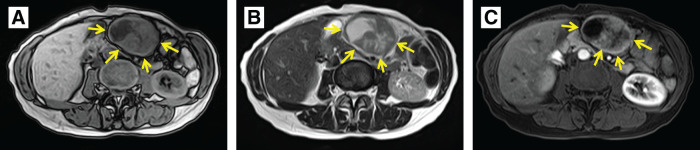

Case presentation: At the age of 44, a 60-year-old female underwent a laparoscopic-assisted proximal gastrectomy for gastric cancer at a previous hospital. Neuroendocrine carcinoma was diagnosed following a postoperative pathological examination based on histological findings and immunostaining results. The patient was followed up without any recurrences. After 14 years, a follow-up contrast-enhanced CT revealed a 9-mm mass on the greater curvature side of the gastric antrum, which was suspected to be lymph node swelling at the previous hospital. After 8 months, she came to our hospital with abdominal discomfort and distention. The CT scan revealed a 55-mm mass, indicating an increase in the previously mentioned mass. At our hospital, the patient underwent open tumor resection. The pathological findings revealed a recurrence of gastric NEC. The patient has been recurrence-free for 6 months following surgery.